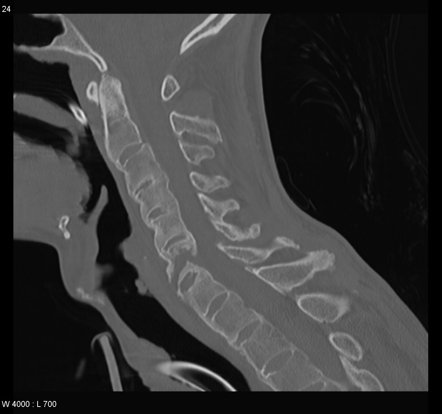

По поводу перелома позвоночника меня еще интересует вопрос.

>>71074650